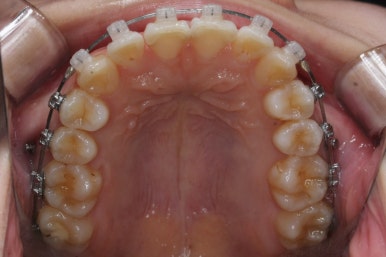

몇 달간의 마무리과정을 거치고 드디어 장치를 제거하였습니다.

위아래 앞니는 다시 틀어지지 말라고 유지철사를 붙였습니다.

위에는 탈착이 가능한 유지장치도 사용합니다. 2중으로 안전장치를 하는 것이죠.

치아는 매우 가지런해졌고, 과개교합도 개선이 되었으며 뻐드러진 앞니 각도도 정상적으로 회복이 되었습니다.